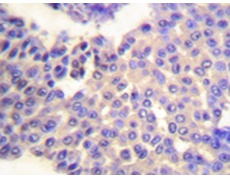

IHC positive control: |

Human breast carcinoma tissue |

IHC Recommend dilution: |

50-100 |